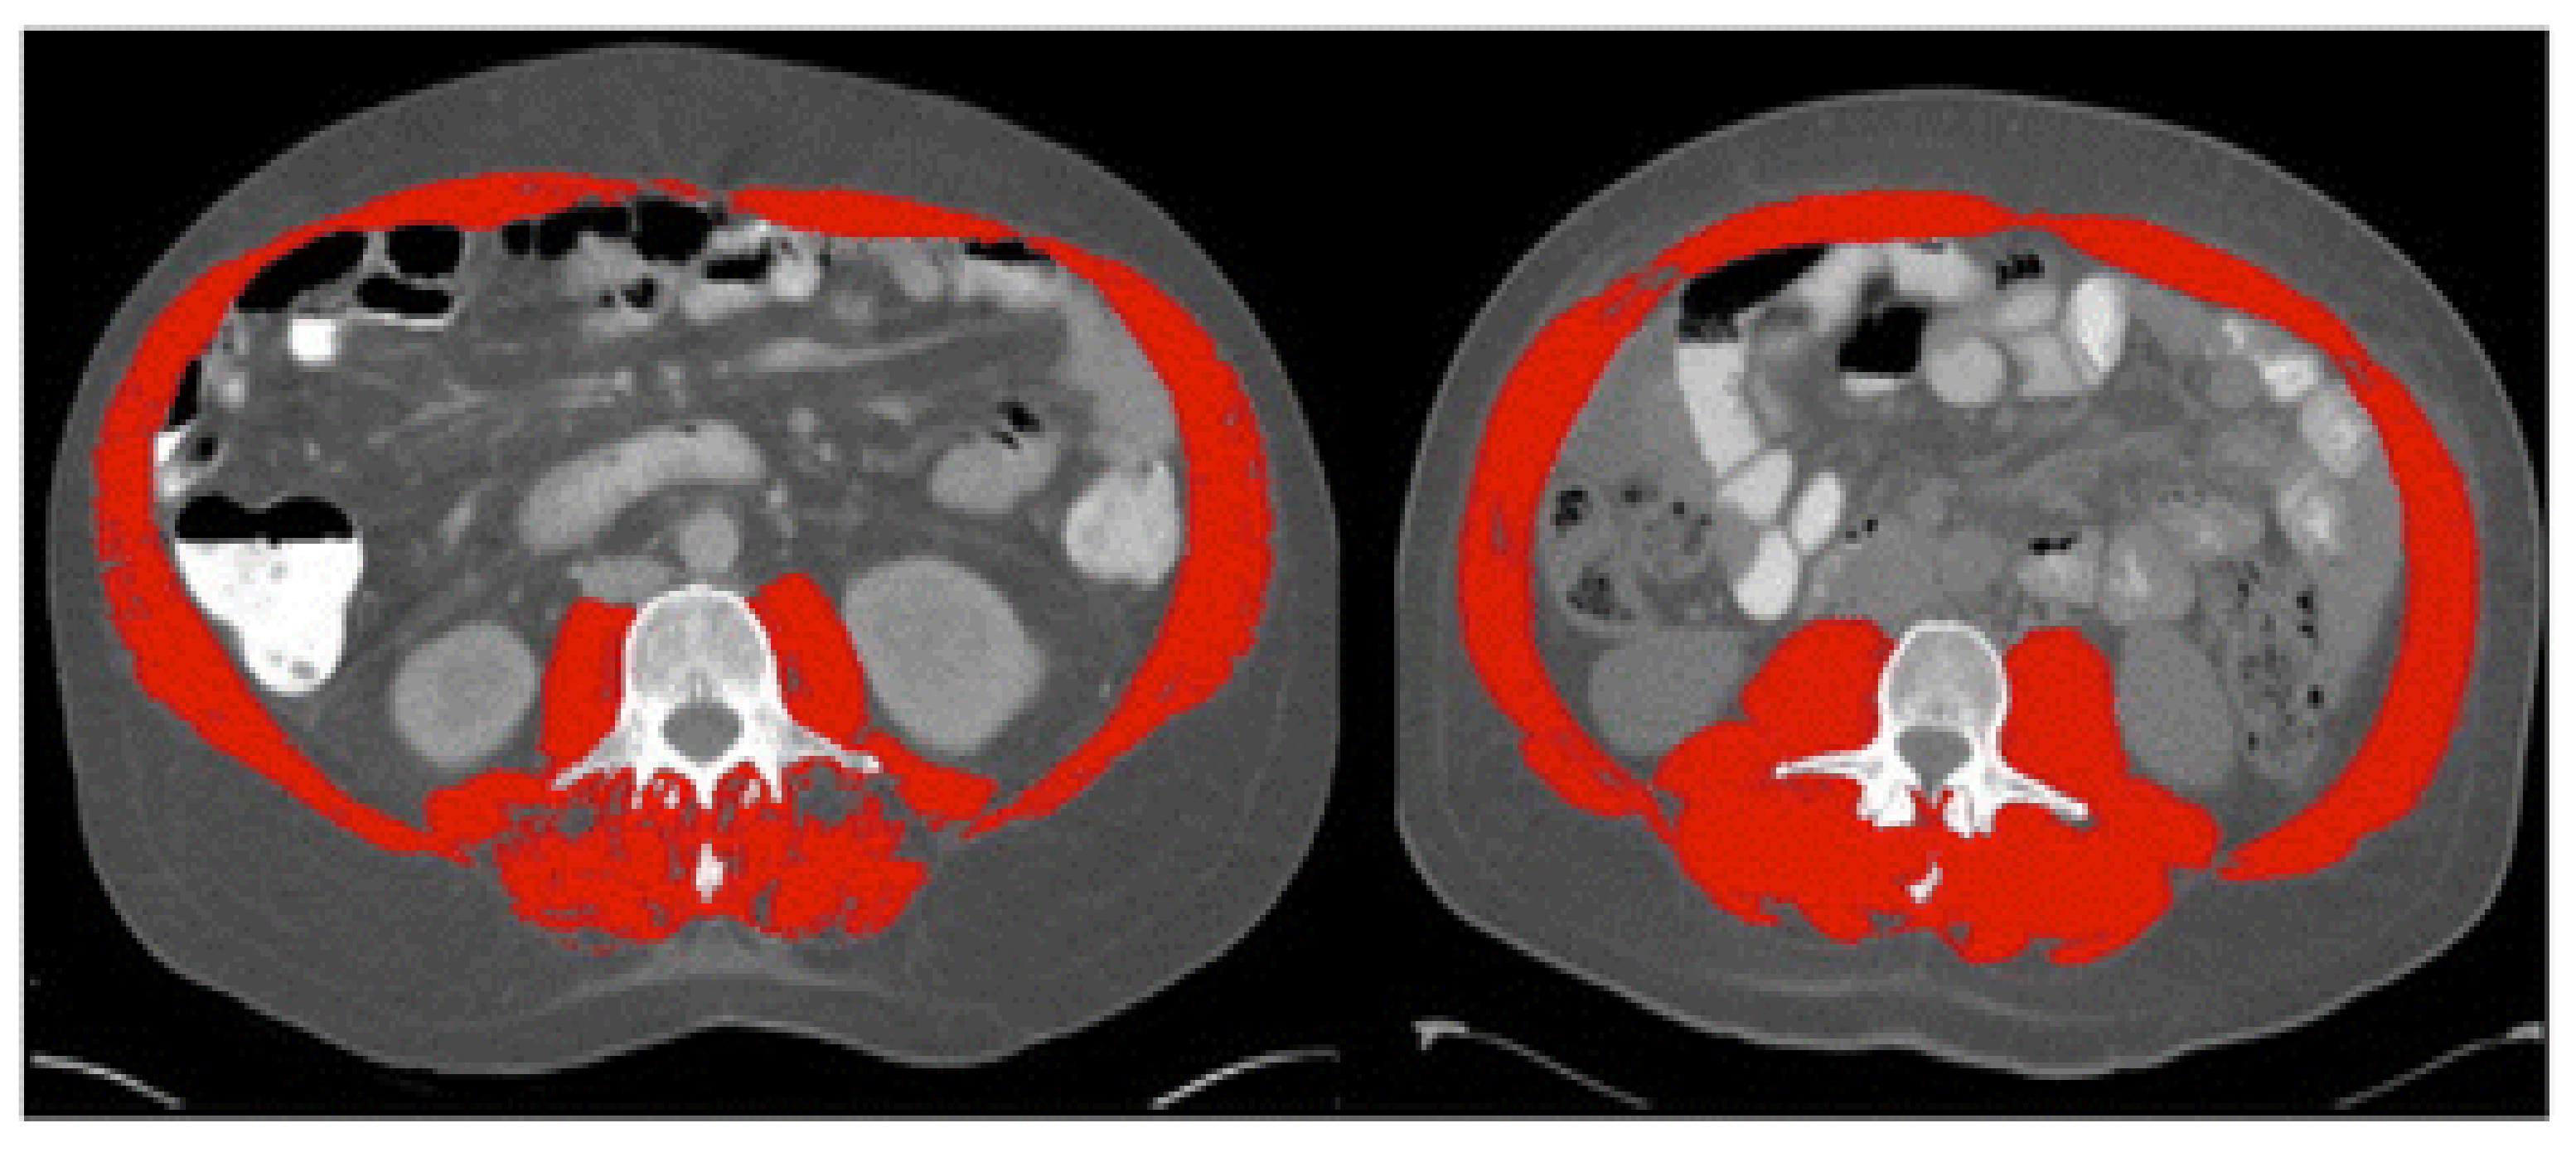

Sarcopenia was first termed in 1989 by Rosenberg et al. as a muscle loss in the aging population [19]. Although several definitions coexist, sarcopenia’s well-adopted description is an age-related process characterized by progressive loss of skeletal muscle mass and function [10]. Several assessment tools can be utilized to assess muscle mass and function (Table 1). To determine the muscle mass, anthropometric measurements, such as the thickness of the skin fold, mid-upper arm muscle circumference (MAMC), and calf circumference have been tried in the past and found to be inaccurate; therefore, these methods are not recommended [20]. Imaging such as computed tomography (CT) at the level of the third lumbar vertebra to assess skeletal muscle index (SMI) (cut-off value of <50 cm2/m2 in men and <39 cm2/m2 in women) and magnetic resonance imaging (MRI) have been used effectively to differentiate between muscle, fat and other soft tissues. However, due to risk of radiation and/or cost, these tests have not been widely used in routine clinical practice [20,21,22] (Figure 1). Instead, dual-energy X-ray absorptiometry (DEXA) is generally recognized as the gold assessment tool to assess the muscle mass in most cases, due to its low cost, low radiation risk of radiation, and reasonable accuracy [23]. Bioimpedance analysis (BIA) can be also used as an affordable alternative method to DEXA [23]. Lastly and importantly, it should be noted that the accuracy of both BIA and DEXA in measuring muscle mass requires patients to be well hydrated prior to undergoing these tests.

Figure 1.

Computed tomography (CT) images at the third lumbar vertebra comparing two patients with cirrhosis and same body mass index but one has sarcopenia and other is not. Left image shows sarcopenia with L3mi of 49.82 cm2/m2. Right image shows non-sarcopenia with L3mi of 70.8 cm2/m2. These abdominal CT images were utilized by Montano-Loza et al. in 2012 and cutoff-values offered by Baumgartner et al. in 1998. Red color denotes abdominal wall muscle, psoas and paraspinal muscles. (Used with permission from Elsevier.).